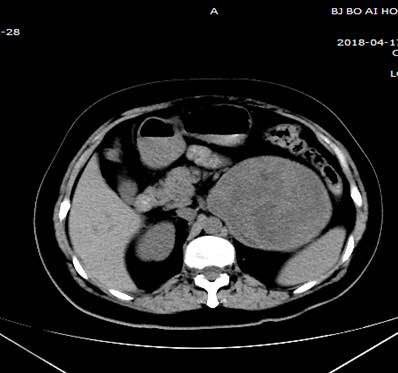

这个肿瘤直径21厘米,长在左侧肾脏上方的位置,周围血管丰富,与下腔静脉、肠系膜上、下静脉、脾动静脉、左肾动静脉关系密切,手术难度极高,术中稍有不慎便会危及生命。

2018年4月23日,王强主任麻醉,徐青主任主刀,第一助手刘文国副主任医师,第二助手石青青医师,第三助手范荣富医师,成功开腹后一个庞然大物出现在医生们的眼前,肿瘤与下腔静脉、肠系膜上、下静脉、脾动静脉、左肾动静脉粘连较重,这些血管像八爪章鱼一样将肿瘤紧密缠绕在中间,肿物内有血肿和血块形成,术中测量肿瘤最大直径达21厘米。徐青主任带领团队成员密切配合,耐心细致的将下腔静脉、肠系膜上、下静脉、脾动静脉、左肾动静脉与肿瘤剥离开来。